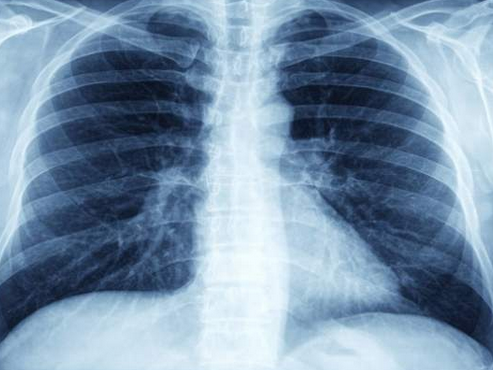

世界卫生组织在28日公布的一份报告中首次表示,结核病与艾滋病一样成为导致人类死亡的首要传染病。 据《路透社》报导,2014年有110万人死于结核病, 同一时期,全球有120万人死于艾滋病,其中有40万人同时染有艾滋病和结核病。 这个报告收集了自从2005年各国和地区在治疗结核病方面所有的数据,其中包括耐药数据,研究和开发以及融资数据。 报告发现,2014年世界卫生组织收到了600万起新结核病病例,比2013年少2/3,2013年全球有960万人患结核病。2014年大约有48万耐多种药物的结核病患,但其中只有1/4被确诊。 该报告还表示,全球对抵抗艾滋病干预的投资是对结核病投资的10倍,其中艾滋病是800万美元,结核病80万美元。 无国界组织临时医疗主任布雷杰登(Dr. Grania Brigden)认为,造成这种投资差异的部分原因在于艾滋病主要在非洲的贫穷国家流行,因此国际投资比较多,而结核病主要在类似于印度和中国这样的国家流行,这些国家往往可以自己资助本国对结核病的治疗,因此国际投资较少。 尽管如此,2015年结核病的治疗方面仍然缺少140万美元费用。 世界卫生组织结核病防治项目主任马里奥(Dr. Mario Raviglione)表示,此报告反应了在过去几十年中对艾滋病的治疗取得了巨大進展,因此救活了很多人,但也反映了国际社会在这两种病的治疗方面的资金投入方面的差别。 他说:“好消息是结核病防治从2000年以来拯救了4300万人的生命,但是考虑到大多数结核病症都是可以被成功救治的,因此这个死亡率仍然是高的令人无法接受。” 他认为为了在遏制类似与艾滋病和结核病这种全球杀手方面取得更多的成功,国际社会应该增加对结核病的投资。 世卫:结核感染与艾滋病一样成为健康主要杀手